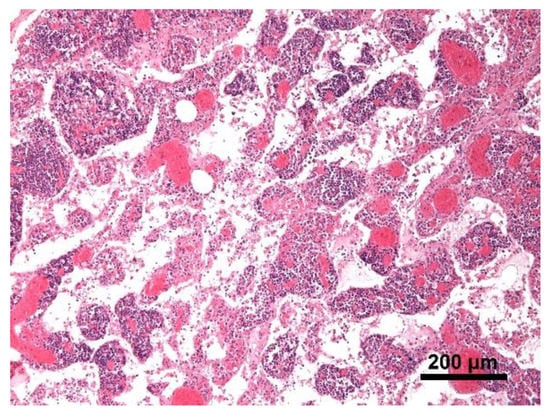

Histology showed severe pulmonary hyperemia and atelectasis, associated with pulmonary edema, alveolar hemorrhages, rare intra-alveolar hemosiderophages, and mild multifocal compensatory emphysema (Figure 8). The thoracic duct was not identified during necropsy. Microscopic examination of the heart failed to detect significant pathological changes. The mediastinal lymph node was microscopically characterized by edema and severe hyperemia associated with a locally extensive hemorrhage (Figure 9). The hemorrhagic nature of intestinal lesions was confirmed histologically. Microscopic examination identified severe and diffuse hyperemia of hepatic centrolobular veins and allowed diagnosis as adenoma of the rete ovarii, a 4 mm nodule detected in the right ovary. Anatomopathological examination identified a cardiogenic shock, secondary to pressure changes developed in the thoracic cavity, as the most likely cause of death of the subject. This hypothesis is supported by the severe multi-organ congestion, caudal vena cava and jugular veins distension, and cyanosis of external mucous membranes.

Figure 8. Lung. Severe pulmonary hyperemia and atelectasis; Hematoxylin and eosin stain, 20× magnification.

Figure 9. Mediastinal lymph node. The lymph node was microscopically characterized by edema and severe hyperemia; Hematoxylin and eosin stain, 10× magnification.